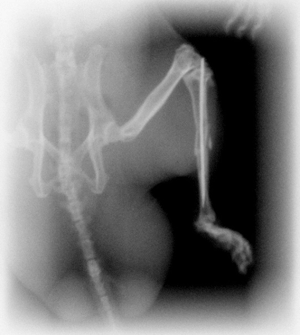

骨折 ハムスターはとても小さいため、ドアに挟まれる、高いところから落ちる、踏まれるなどの事故で骨折するケースが多く見られます。骨折の状況に応じて、手術で治したり、包帯を巻いて回復を待ちます。 |

![]() 骨折した足の写真です。 |

![]() 骨折の手術後のレントゲン写真です。 |